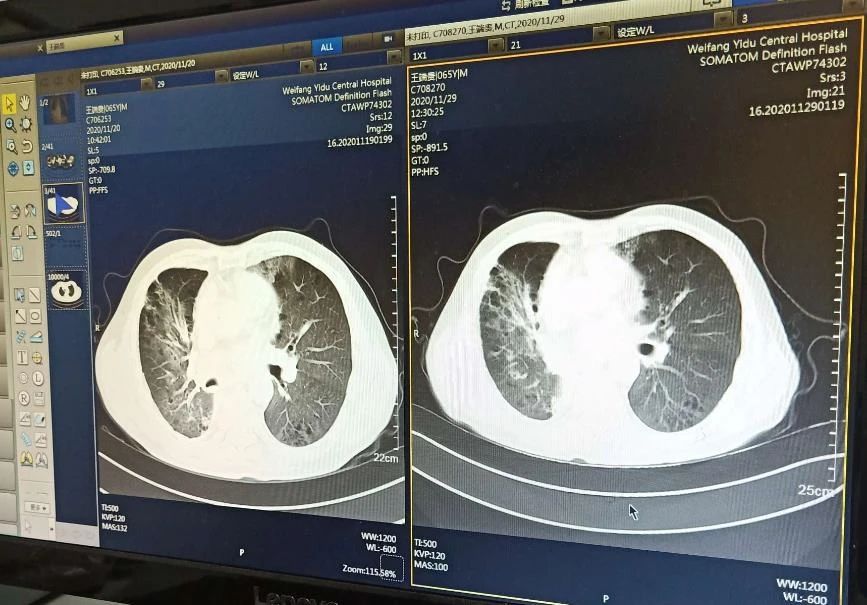

直接注射法治疗临床案例

2018年中国医学科学院肿瘤医院等单位的研究人员在一项名为“自体骨髓间充质干细胞治疗难治性肺纤维化的研究”(NCT02645149)的临床试验中,使用自体骨髓间充质干细胞治疗了4例肺纤维化患者。

这4例患者的年龄分别为41岁、51岁、54岁和64岁,其中3例为女性,1例为男性。这些患者都曾经接受过多种药物和治疗,但病情仍未得到控制。

在干细胞治疗前,研究人员对这些患者进行了详细的评估,包括呼吸功能、症状严重程度、肺功能和生活质量等指标。治疗过程中,研究人员从患者自身骨髓中采集间充质干细胞,经过扩增后直接注射到患者的静脉血管中。每个患者每次注射的干细胞剂量为1×106个/kg体重。

治疗后,研究人员对患者进行了长期的随访和观察。结果显示,干细胞治疗可以显著改善患者的肺功能和生活质量。具体来说,4例患者在治疗后的3个月和6个月时的呼气容积、肺活量和肺弹性均值等指标均显著改善。此外,患者的症状也有所缓解,生活质量得到明显提高。治疗期间,没有发现明显的副作用和并发症。